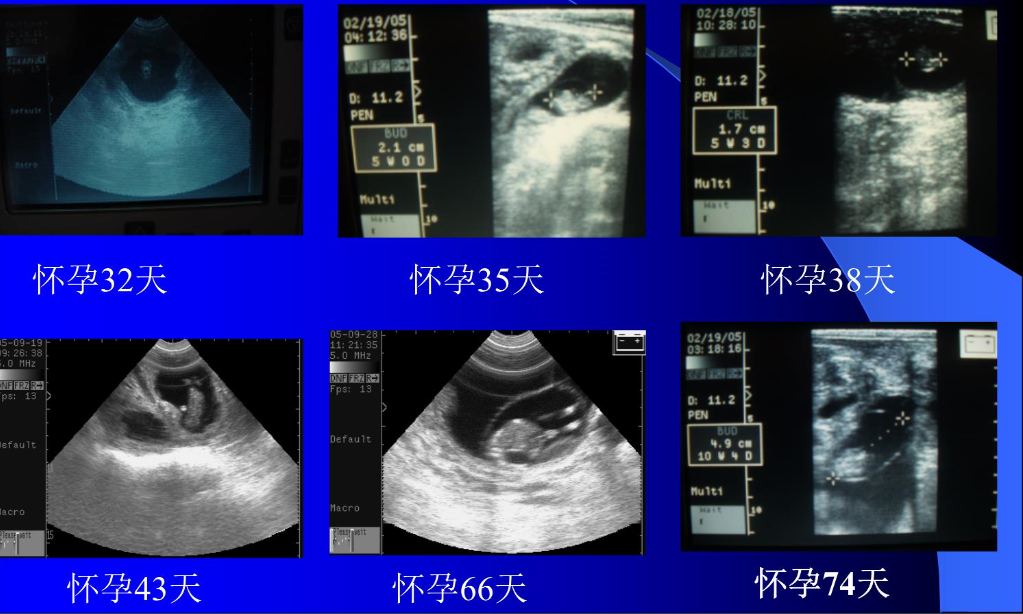

经直肠实时超声在母牛繁殖研究中的应用代表了一项技术突破,彻底改变了生殖生物学知识。通过超声成像产生的新研究信息阐明了牛复杂生殖过程的性质,包括卵巢卵泡动力学、黄体功能和胎儿发育。超声技术在母牛繁育的早期整合包括诸如经阴道卵泡抽吸和卵母细胞回收等应用,以及作为胚胎移植程序的补充技术。